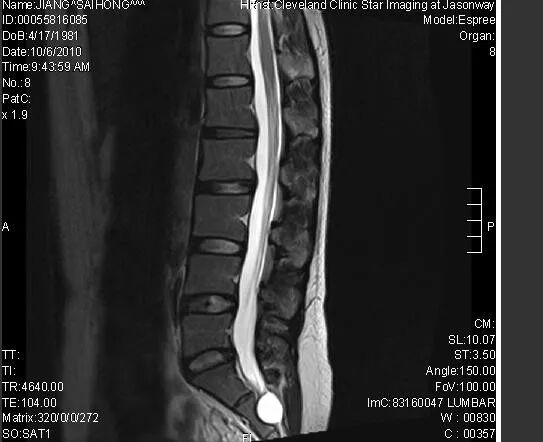

最好是有一个清楚的核磁和X线片:排出来的核磁你自己放大后看看周围的英文字母是否清楚,如果不清楚,重新拍照。拍照具体的方法的将照片放在电脑屏幕或者白天的玻璃窗户上,用手机进行拍摄。

合格的照片如下图,周围的英文字母清晰即可